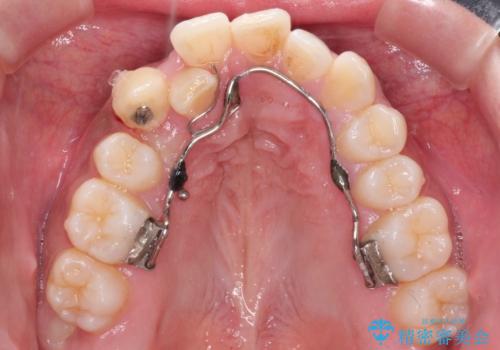

インビザラインでの治療がご希望でしたが、右上の歯のかさなりが強いところは、補助装置である程度動かしてからインビザラインに移行することにしました。

インビザラインだけで歯を動かすよりも、補助装置を併用することにより効率的に、短期間で治療を行うことができる場合があります。